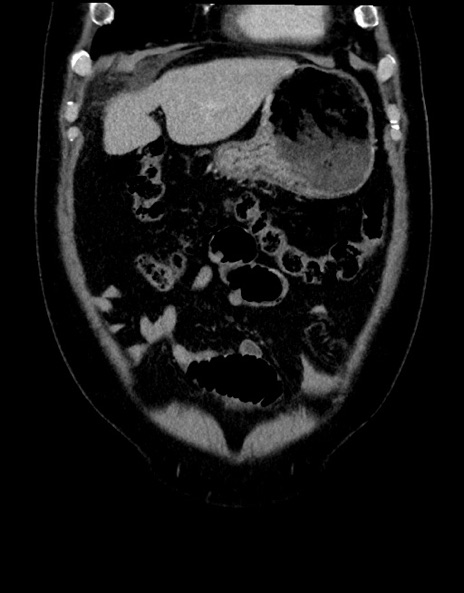

症例15(冠状断像)

【症例】70歳代男性

【主訴】腹痛

【現病歴】今朝から腹痛あり。全体的に痛い。特に左上の方。排ガスが今日はない。冷や汗が出る。

【既往歴】直腸癌術後

【身体所見】左側腹部〜上腹部に圧痛あり。腹膜刺激症状明らかなではない。軽度反跳痛。左下腹部に術後瘢痕あり。

【データ】WBC 7700、CRP 0.02